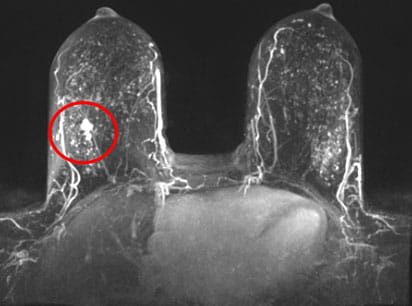

Program has identified 19.9 breast cancers per 1,000 studies

One-year data show that the abbreviated breast MRI program at UH has identified 19.9 breast cancers per thousand studies, Dr. Marshall says.

“That’s really, really good,” she says. For comparison, a prospective, multi-institutional study published last February in JAMA showed that abbreviated breast MRI detected 11.8 cancers per thousand studies.